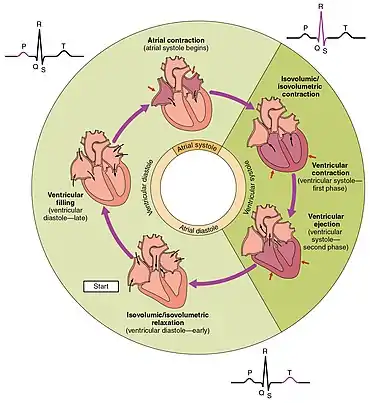

The cardiac cycle is the sequence of events in which the heart contracts and relaxes with every heartbeat.[11] The period of time during which the ventricles contract, forcing blood out into the aorta and main pulmonary artery, is known as systole, while the period during which the ventricles relax and refill with blood is known as diastole. The atria and ventricles work in concert, so in systole when the ventricles are contracting, the atria are relaxed and collecting blood. When the ventricles are relaxed in diastole, the atria contract to pump blood to the ventricles. This coordination ensures blood is pumped efficiently to the body.[7]

At the beginning of the cardiac cycle, the ventricles are relaxing. As they do so, they are filled by blood passing through the open mitral and tricuspid valves. After the ventricles have completed most of their filling, the atria contract, forcing further blood into the ventricles and priming the pump. Next, the ventricles start to contract. As the pressure rises within the cavities of the ventricles, the mitral and tricuspid valves are forced shut. As the pressure within the ventricles rises further, exceeding the pressure with the aorta and pulmonary arteries, the aortic and pulmonary valves open. Blood is ejected from the heart, causing the pressure within the ventricles to fall. Simultaneously, the atria refill as blood flows into the right atrium through the superior and inferior vena cavae, and into the left atrium through the pulmonary veins. Finally, when the pressure within the ventricles falls below the pressure within the aorta and pulmonary arteries, the aortic and pulmonary valves close. The ventricles start to relax, the mitral and tricuspid valves open, and the cycle begins again.[11]